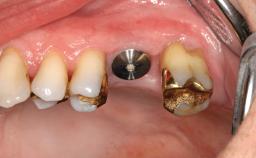

Combined SFE and Horizontal Ridge Augmentation with Autologous Block Grafts, BCP, and GBR using a Staged Approach

Various patterns of alveolar bone resorption are known to occur in the posterior maxilla. Following tooth loss, resorption may take a buccopalatal direction, resulting in a narrow ridge displaced toward the palate. Resorption may also proceed vertically in an apical direction, reducing the vertical dimension of the ridge and increasing the interocclusal space. Another common pattern of atrophy is caused by volume increases of the maxillary sinus, which will reduce the residual bone volume in an occlusal direction due to downward displacement of the sinus floor. Most cases are characterized by combined defects, leading to a variety of atrophy configurations. Whenever there is a greater need for augmentation than elevating the sinus floor with an inlay bone graft, horizontal and vertical augmentation of the residual ridge may be accomplished by intraoral harvesting of autologous onlay block grafts in the same surgical procedure. We refer to this procedure as “inlay-onlay” grafting of the posterior maxilla.